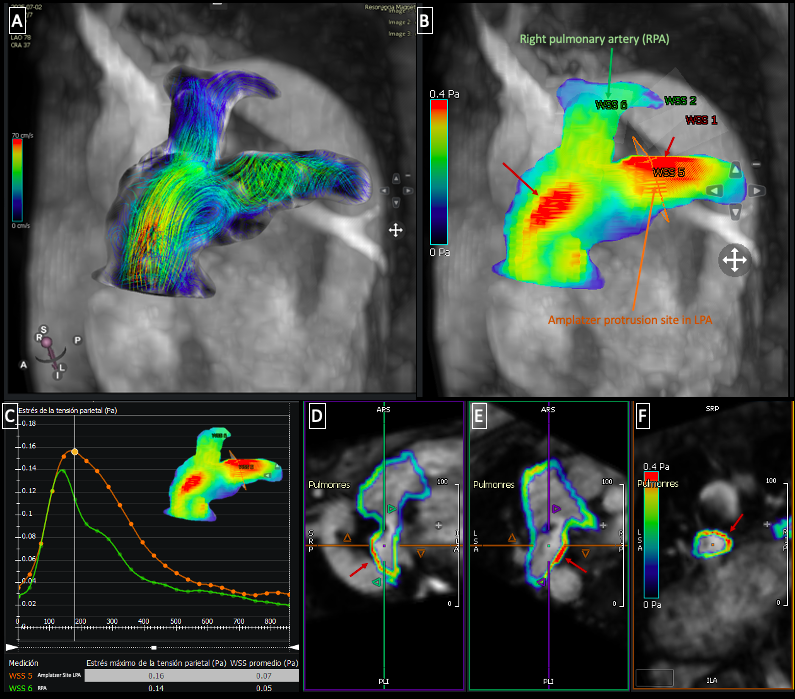

Fig. 2 4D Flow in the pulmonary artery: A) Pathline visualization demostrating flow acceleration along the anterior wall of the main pulmonary artery and turbulent flow at the origin of the left pulmonary artery (LPA). B) Regions of increased shear wall stress highlighted (red arrows). C) Quantitive analysis in pascals (Pa) comparing both pulmonary branches. D-F) Multiplanar reconstructions depicting the site of device protrusion into the proximal LPA.

Fig. 2 4D Flow in the pulmonary artery: A) Pathline visualization demostrating flow acceleration along the anterior wall of the main pulmonary artery and turbulent flow at the origin of the left pulmonary artery (LPA). B) Regions of increased shear wall stress highlighted (red arrows). C) Quantitive analysis in pascals (Pa) comparing both pulmonary branches. D-F) Multiplanar reconstructions depicting the site of device protrusion into the proximal LPA. Fig. 3 4D Flow in the aorta: A) Pathline visualization demostrating flow acceleration in the ascending aorta and turbulent flow at the site of device protusion. B) Regions of increased wall shear stress (red arrows). C) Quantification in pascals (Pa) comparing wall shear stress before the device and at the device site. D-F) Multiplanar reconstructions illustrating the location and extent of the device protrusion within the aortic lumen.